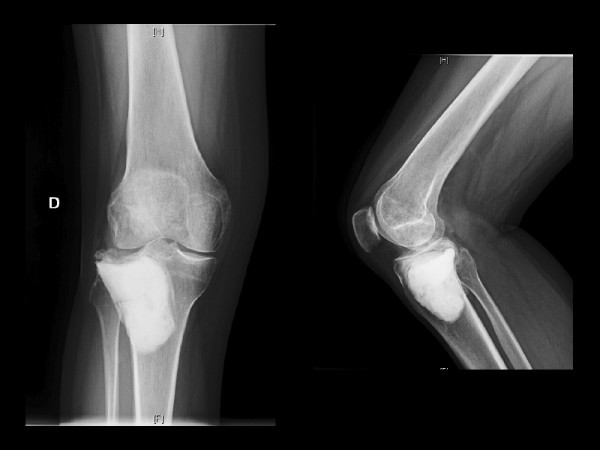

Varón de 39 años

- Dolor +impotencia funcional 3 meses

- Biopsia Trucut+TCG

- Dolor de intenso en incapacitante en rodilla D

- Diagnóstico de TCG, tratamiento con curetage no posible de entrada.

- Mejoría del dolor a la 4 semanas de tratamiento con denosumab